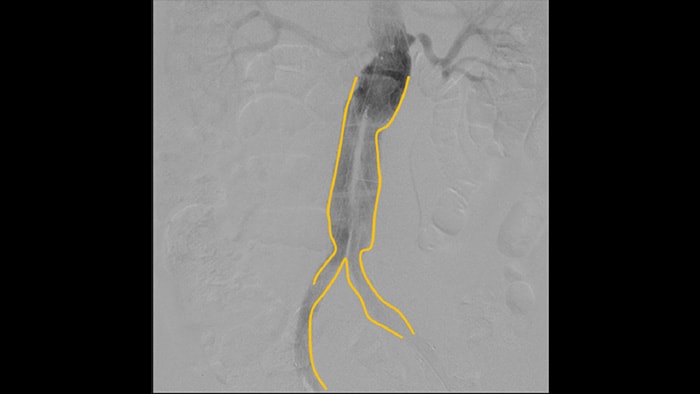

With the Zenition, our DSA image quality has improved greatly. We no longer see a grainy image. We just see a very clear image."

Digital subtraction angiography (DSA) is used in interventional vascular procedures to clearly visualise blood vessels by removing structures that can obscure vessel visibility. Roadmap fluoroscopy overlays a previously acquired subtracted contrast image on the live fluoroscopy, allowing you to track a device without reinjecting contrast.

Use the Outlining tool to easily mark a bifurcation or side branches by simply drawing on the monitor of the Mobile Viewing Station with your finger or an externally connected mouse.